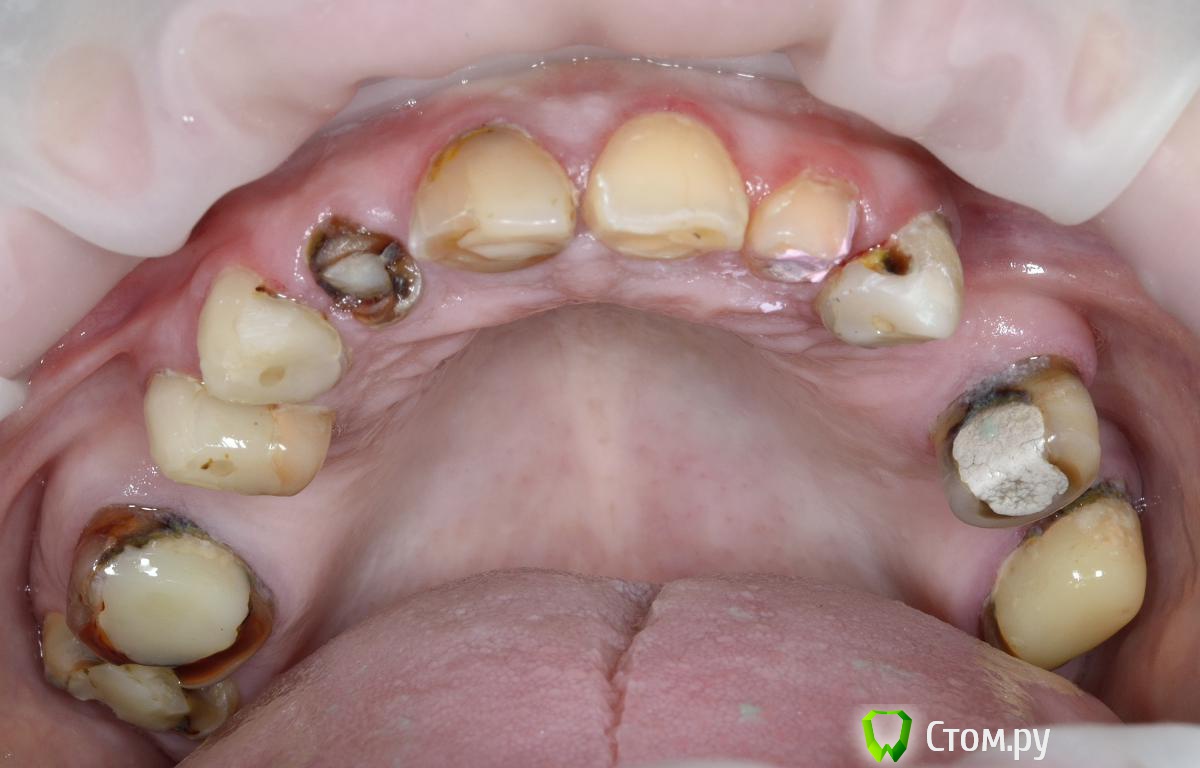

Vitremer Опубликовано 13 июля, 2014 Поделиться Опубликовано 13 июля, 2014 Здравствуйте! Пациентка 37 лет. Тотальное протезирование в/ч.Что делать:1.с уже ранее леченными и восстановлеными СВШ зубами 1.4 1.3 2.3 2.7 ? ( оставлять-менять на вкв...)2. корень 1.2 . ВКВ ? феррула почти нетПока такие вопросы. Ссылка на комментарий

Vitremer Опубликовано 13 июля, 2014 Автор Поделиться Опубликовано 13 июля, 2014 Я бы всё убрал - и сделал заново Снимки в понедельник.Заново чем?- вкв , анкера, билд-апы по Бабурову? (я так вижу кругового феррула нет) Ссылка на комментарий

M@estro Опубликовано 13 июля, 2014 Поделиться Опубликовано 13 июля, 2014 Заново чем?- вкв , анкера, билд-апы по Бабурову? (я так вижу кругового феррула нет) Анкера в топку,остальное- оценил бы ,что там от зубов осталось после того,как убрал. Сложно судить,но что -то мне подсказывает,что покрывать всё это в нынешнем состоянии - это не совсем правильно и не совсем надолго Ссылка на комментарий

dzynya Опубликовано 14 июля, 2014 Поделиться Опубликовано 14 июля, 2014 бы предложила хирургическое удлинение, для начала Ссылка на комментарий